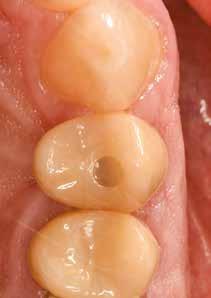

Az eljárást helyi érzéstelenítés mellett végeztük (4%-os articaine-hidroklorid 1:100 000 adrenalinnal). Papillakímélő, U alakú palatális bemetszést végeztünk, teljes vastagságú nyálkahártyalebeny preparálás történt, a lebenyt bukkálisan feltekertük (5. ábra). A lebeny bukkálisan feltekert részén de-epitelizációt végeztük el, amellyel kompenzálni tudtuk a bukkális lágyszöveti defektust. Szakaszos előfúrást végeztünk, és a bredent copaSKY 4x10 implantátumot 30 Ncm behajtási nyomatékkal helyeztük be (6. ábra). Az implantátumot 1 mm-re szubkresztálisan helyeztük be, hogy később szélesebb emergenciaprofilt tudjunk kialakítani (7. ábra). Az egyedi ínyformázó úgy készült, hogy kompozitot vittünk fel a titánbázisra, és így formáztuk a lágyszöveteket a transzgingivális gyógyulási fázis során (8. ábra). Az egyéni ínyformázó tulipán formájú, hogy kialakítsa a kívánt emergenciaprofilt. A lágyszövetet feszülésmentesen zártuk #6/0 nem felszívódó, monofil fonallal (Optilene, B. Braun Deutschland; 9. a–b. ábra). Posztoperatív röntgenfelvétel készült, ami alapján az implantátum a szomszédos fogakkal párhuzamos elhelyezést mutatott (10. ábra). Posztoperatív utasításokat adtunk a páciensnek a műtéti terület körüli szájhigiénia fenntartása érdekében. A beavatkozást követő egy héttel a varratokat eltávolítottuk, és a kezelt terület kielégítő gyógyulást mutatott (11. ábra). A 4 hónap utáni késleltetett terhelést a páciens kívánsága szerint terveztük.

A teljesen digitalizált protetikai munkafolyamat során az Exocad szoftver segítségével (exocad) egy hibrid, csavarrögzített, cirkónium monolit koronát gyártottunk le copaSKY

uni.fit titánalapra (bredent medical). Az implantátum körül a bukkális lágyszövet megfelelő vastagságot és kedvező ínykontúrt mutatott (12. a–b. ábra). Az egyedi ínyformázó eltávolítása után egészséges implantátum körüli lágyrészgallér

értünk el (19. ábra). Az okkluzális nyílást tefloncsíkkal és kompozittal zártuk (20. ábra). Mindezek után, posztoperatív kontroll röntgenfelvétel készült, amely a pótlás megfelelő illeszkedését mutatta (21. ábra). A hat hónapos utánkövetés során jól megfigyelhető a teltebb lágyszöveti profil és a megtartott kresztális csontszint (22–24. ábra)

18. ábra: Végleges, hibrid, csavaros rögzítésű, monolit cirkóniumkorona titánalapon, fényezett ínygallérral.

használatát, és jobb kommunikációt tesznek lehetővé a fogtechnikai laborral [10]. Ebben az esetben egy hibrid csavarrögzített pótlást terveztünk és kiviteleztünk. Egy átfogó áttekintés, amely a csavarozható és ragasztott koronák klinikai jelentőségére összpontosított a döntéshozatalban, azt állapította meg, hogy a csavaros rögzítésű pótlás kevesebb biológiai szövődményt mutat, illetve előnye, hogy könnyen javítható anélkül, hogy károsítaná az ínyformázót és a koronát [11]. A cementtel rögzített korona eltávolítása még mindig nagyobb kihívást jelent és kevésbé kiszámítható, mint egy csavaros pótlásé [11]. Így a csavarozható pótlás leegyszerűsíti a kezelést, amennyiben a jövőben bármilyen komplikáció lépne fel. A cement kifolyása és az implantátum körüli mucosa alatt maradása mikrobiális kolonizációt és az implantátum körüli szövetek károsodását eredményezheti. A csavarrögzített pótlásokkal könnyebben megoldható a szájhigiénia, és egyszerűbben elvégezhetők a fenntartó kezelé-

sek [12]. A végleges pótláshoz polírozott, teljes kontúrú (full contour) cirkóniumkoronát használtunk. A réteges cirkóniumkoronákban a leplezőkerámia hosszan tartó kopás után berepedezést vagy akár leválást mutat, ami a helyreállítás meghibásodását eredményezi [13]. A monolit koronák CAD/ CAM technológiával készülnek, nagy a hajlítószilárdságuk és törésállóságuk, nagyobb, mint az alumínium-oxid alapú kerámiakoronáké [14].